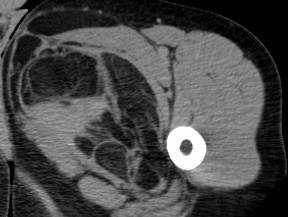

Liposarcome bien différencié. Noter la masse graisseuse, ayant une composante tissulaire (flèches) et des septas épais rehaussés après injection de gadolinium